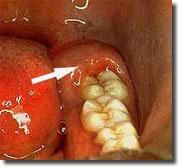

Tumbuhnya gigi geraham seringkali terasa sakit.

Hal ini karena untuk tumbuh gigi geraham sangat penting fungsinya untuk mengunyah dan menggiling makanan. Gigi geraham bungsu merupakan rangkaian gigi yang terakhir tumbuh. Cara mengobati sakit gigi sebenarnya sangat mudah dilakukan. Sakit gigi adalah rasa sakit pada gigi atau area di sekitarnya.